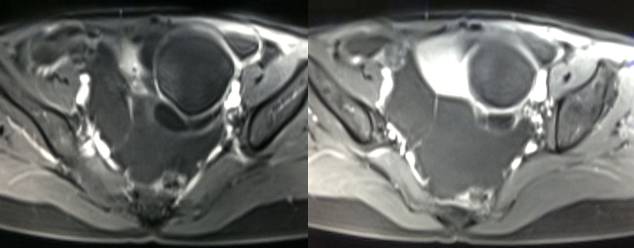

女性,42岁。

主诉:下腹部胀痛不适1月余

病史:自诉13岁时患“结核”,8年前行“左侧附件包块”切除术。

病理结果:黄体血肿

根据时间不同MR信号也有所不同,TIWI脂肪抑制序列可以鉴别脂肪和出血。

畸胎瘤:多呈囊性或囊实性,单房或多房状,囊内液体可有分层,实质由多胚层组织构成,MR 信号不均,肿块内见脂肪信号有利于畸胎瘤的诊断。

巧克力囊肿:常呈多发的单囊或多囊改变,病灶大小不等,囊壁厚薄不均,囊内信号复杂,囊内或各囊腔间血液因出血时期不同,信号常呈多样性,囊肿内反复出血、破裂,形成相互粘连的多房性囊肿,是其较为特征性的表现。

在鉴别卵巢畸胎瘤、出血性囊肿或巧克力囊肿时,MR 脂肪抑制T1WI 可明确肿块内高信号成分是脂肪还是出血,同时由于脂肪组织与非脂肪组织的共振频率不同,在两者交界处沿磁场频率编码方向出现化学位移伪影,但出血性囊肿与巧克力囊肿的鉴别有时较为困难。